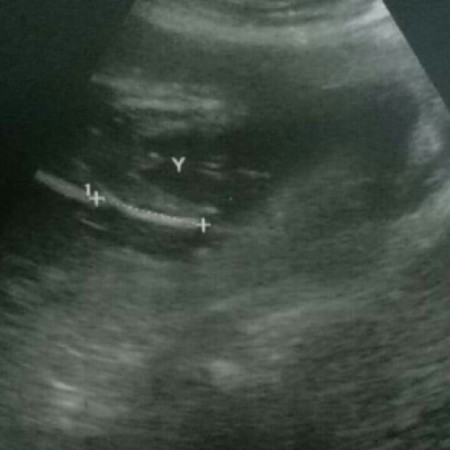

เพศไหนเอ่ย??

บ้านไหนดูออกบ้างว่าแบบนี้น้องผู้ชายชัวร์มั๊ยค่ะแม่ แอบลุ้น ช่วยดูให้แม่หน่อย?? ซาวน์ตอน 20week ขอบคุณสำหรับคำตอบค่า??

น่าจะผู้ชายค่ะ